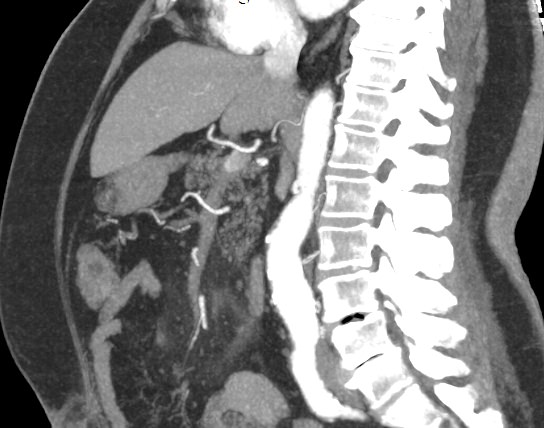

Компьютерная томография позволяет детально визуализировать структуру лимфатических узлов, выявить ее неоднородность, гиперплазию, определить деформацию контуров, появление инфильтрации окружающих тканей с образованием пакетов и конгломератов лимфоузлов.

Полученные данные посредством инновационных цифровых приложений преобразуются в трехмерные изображения высочайшего качества, что позволяет проводить точную и достоверную диагностику.

С целью повышения контрастности изображений, выявления патологических изменений в лимфоузлах дополнительно внутривенно вводится рентгеноконтрастное вещество на основе йода. Контраст накапливается в патологических очагах и под воздействием рентгеновских лучей обусловливает их яркое изображение на фоне неизмененной ткани. Контрастирование значительно повышает диагностическую ценность исследования и помогает выявлять многие серьезные заболевания на начальных этапах.